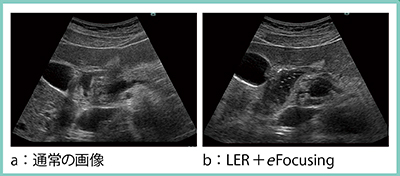

1.LERとの併用における有用性

eFocusingは,前述の画像調整機能と併用することでコントラストが明瞭となるため非常に有用となる。図3は,十二指腸〜膵頭部の画像であるが,通常の画像(a)と比較し,LERをオンにすることで黒が際立ち,さらにeFocusingをオンにすると浅部の描出が向上し,輪郭にメリハリのある引き締まったきれいな画像となっている(b)。

図3 LERとの併用におけるeFocusingの有用性(十二指腸〜膵頭部)